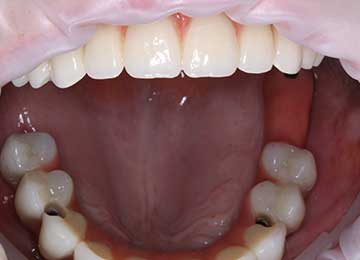

Имплантация зубов: фото "До" и "После"

Фото ДО

Фото ПОСЛЕ

Наведите для просмотра

All-on-4